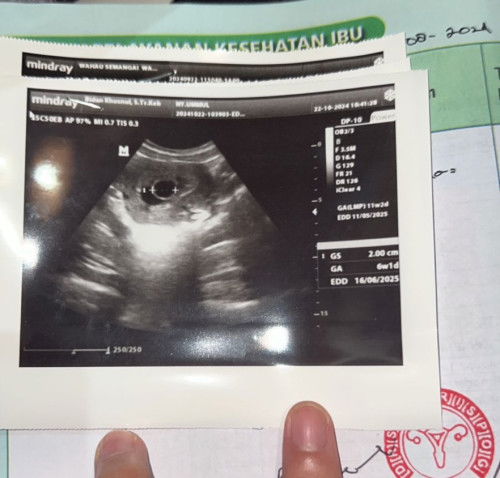

usg tdk sesuai hpht terancam tidak berkembang

klo dri hpht harusnya sdh 11w, karna dari kemarin keluar flek terus sm gumpalan” coklat jdi langsung usg pagi tdi. uk 6w beda jauhh dri hpht . dari usg minggu lalu usianya jg tetap di 6w yg mna harusnya bertambah. masih kupertahanin ga mau lngsung kuret. jika memang bukan rezekiku inshaAllah sdh ikhlas apapun yg terjadi nanti#firstmom #usg